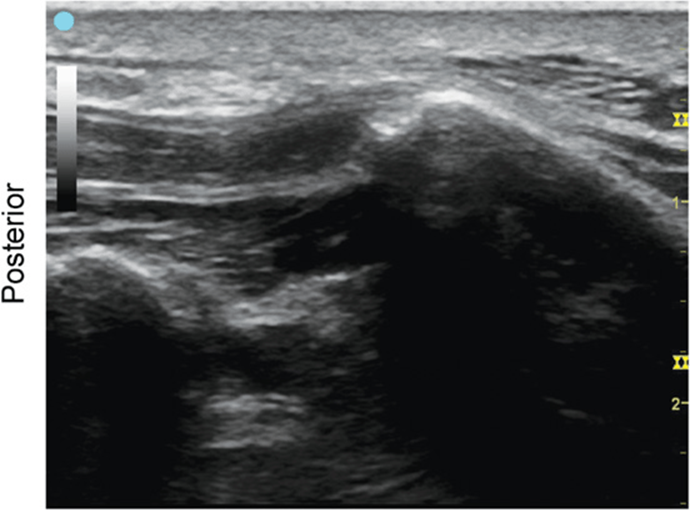

Maxillary Nerve

FIGURE 7.3.1A Ultrasound transducer position to image the maxillary nerve.

FIGURE 7.3.1B Ultrasound image of maxillary nerve.

FIGURE 7.3.1C Labeled ultrasound anatomy of maxillary nerve, transverse view.